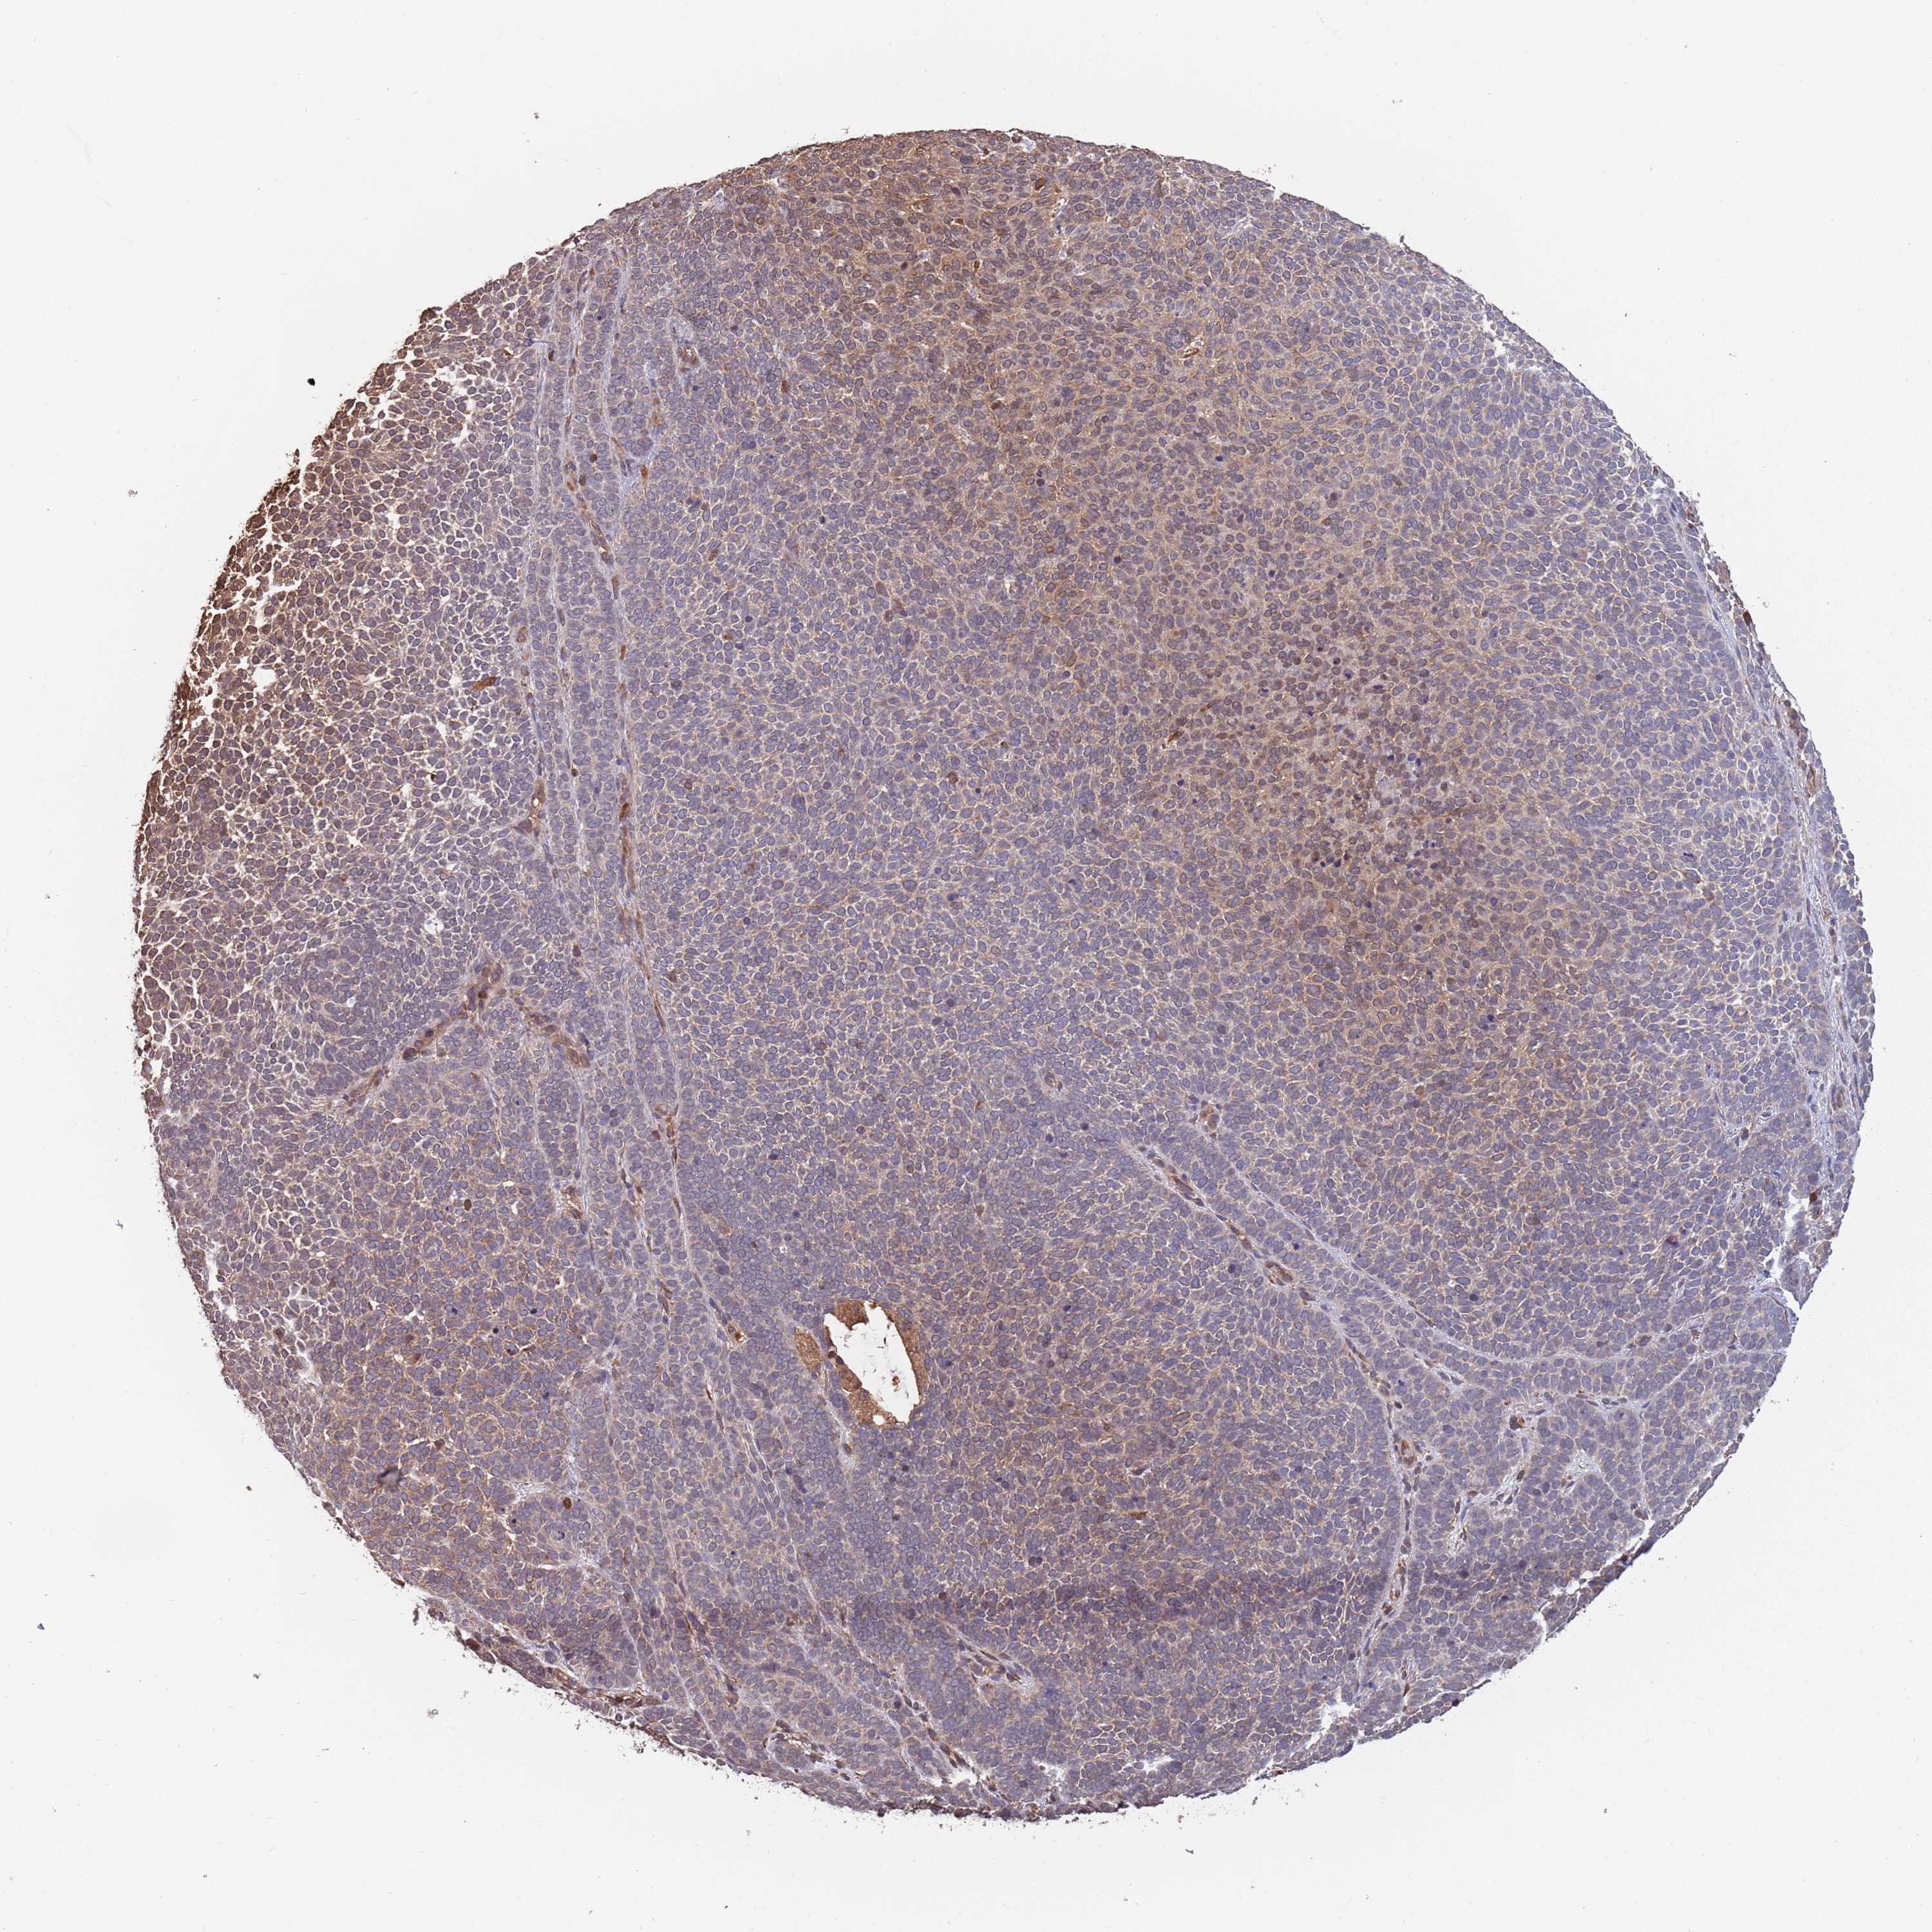

SKIN CANCER - Protein expressioni

A mouse-over function shows sample information and annotation data. Click on an image to view it in a full screen mode. Samples can be filtered based on level of antibody staining by selecting one or several of the following categories: high, medium, low and not detected. The assay and annotation is described here.

Antibody stainingi

Antibody staining in the annotated cell types in the current human tissue is reported as not detected, low, medium, or high, based on conventional immunohistochemistry profiling in selected tissues. This score is based on the combination of the staining intensity and fraction of stained cells.

Each image is clickable and will lead to virtual microscopy that enables deeper exploration of all samples and also displays staining intensity scores, fraction scores and subcellular localization as well as patient and tissue information for each sample.

Antibody HPA040924

Antibody HPA042539

Staining

High

Medium

Low

Not detected

Intensity

Strong

Moderate

Weak

Negative

Quantity

>75%

75%-25%

<25%

None

Location

Nuclear

Cytoplasmic/membranous

Cytoplasmic/membranous,nuclear

Basal cell carcinoma

Squamous cell carcinoma, NOS

Squamous cell carcinoma, metastatic, NOS